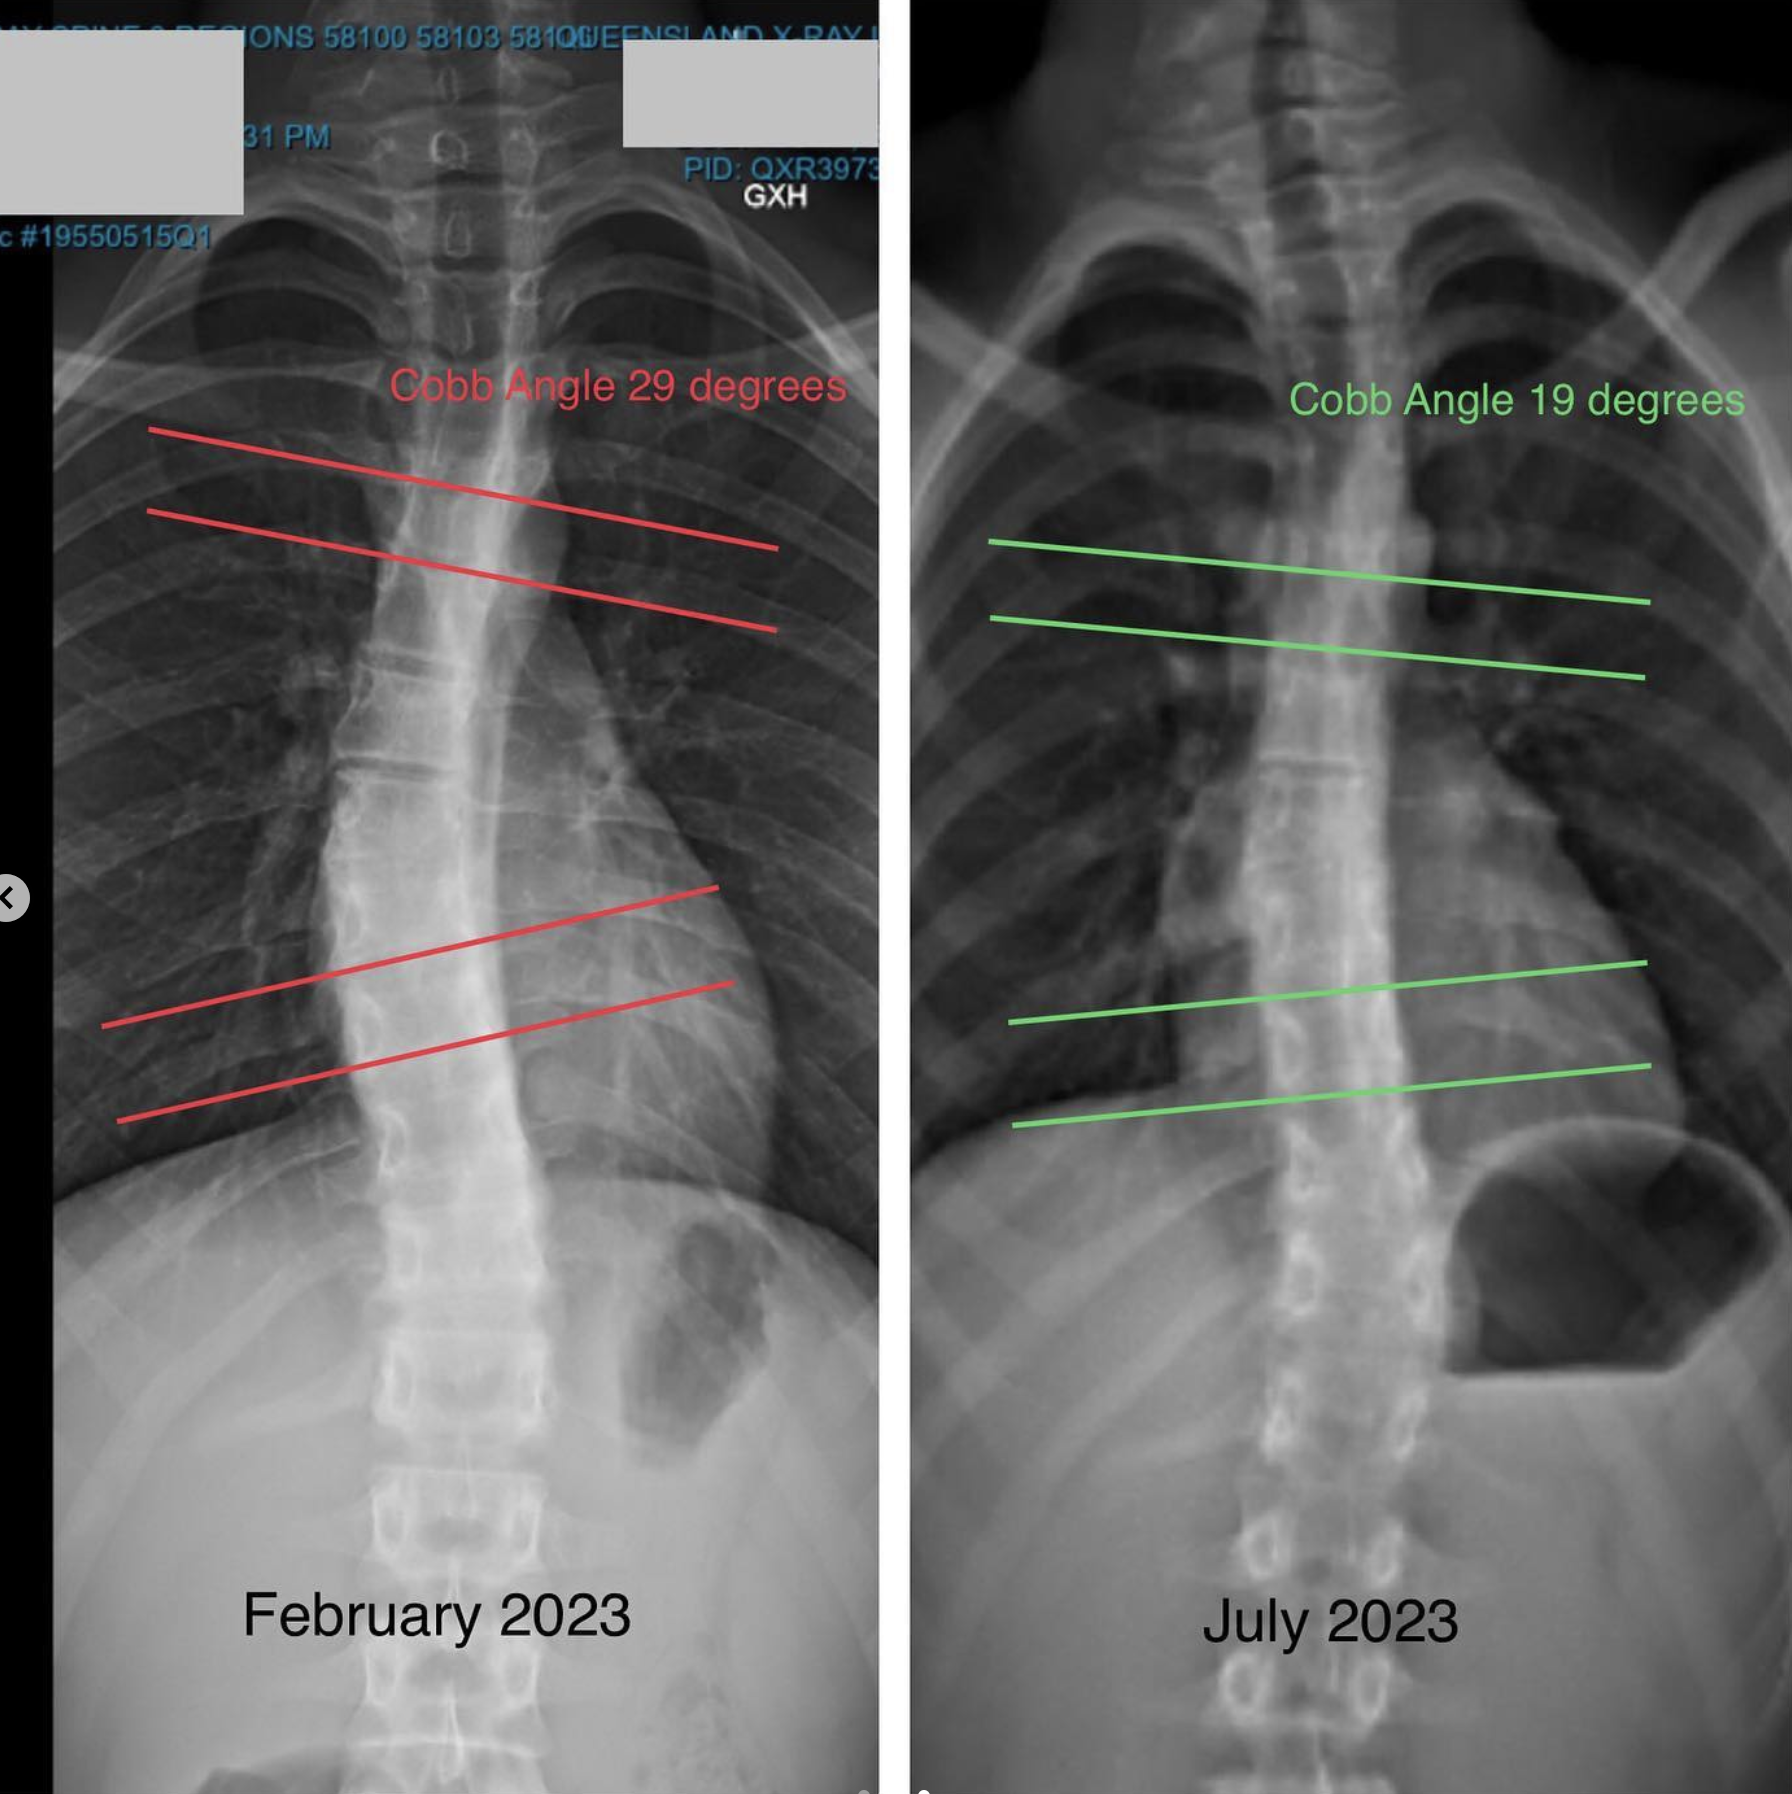

Before - 27/2/2023 -> After - 29/1/2024

- 29 degree Cob Angle

- 19 degree Cob Angle

X-RAYS

Before - February 2023

After - July 2023

This is a reduction in Cobb Angle of 10 degrees.

Because this reduction was achieved through a change in movement patterns, it is likely that it will be a lasting reduction.

We see that reductions caused by methods such as a scoliosis brace or surgery have a higher chance of relapsing.

This is because passive methods fail to address the root cause of the scoliosis.